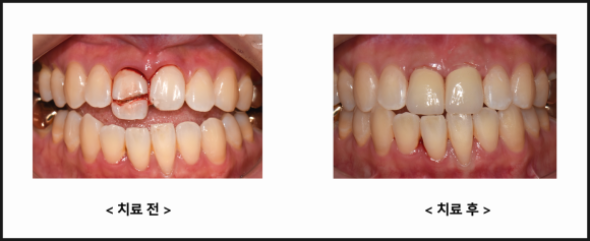

1. Is the preservation of natural teeth the top priority?

Unlike other parts of our body, teeth do not regenerate after being lost.

Therefore, before deciding to extract a tooth, it's important to carefully consider various preservation treatment options and determine the direction of treatment.

Of course, if inflammation is affecting surrounding teeth, the situation is different. However, it's best to choose a clinic with a 'treatment philosophy' that prioritizes tooth preservation.